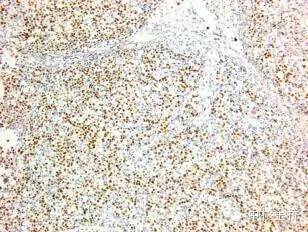

圖為EBER原位雜交染色DBA顯色,蘇木素復(fù)染

EBER是EB病毒編碼的小RNA,在EB病毒感染的細(xì)胞核中高拷貝存在。根據(jù)EBER的序列設(shè)計(jì)的EBER RNA探針,可以用于石蠟切片,具有較高的特異性和靈敏度,該試劑盒廣泛應(yīng)用于美國、歐盟等各國。